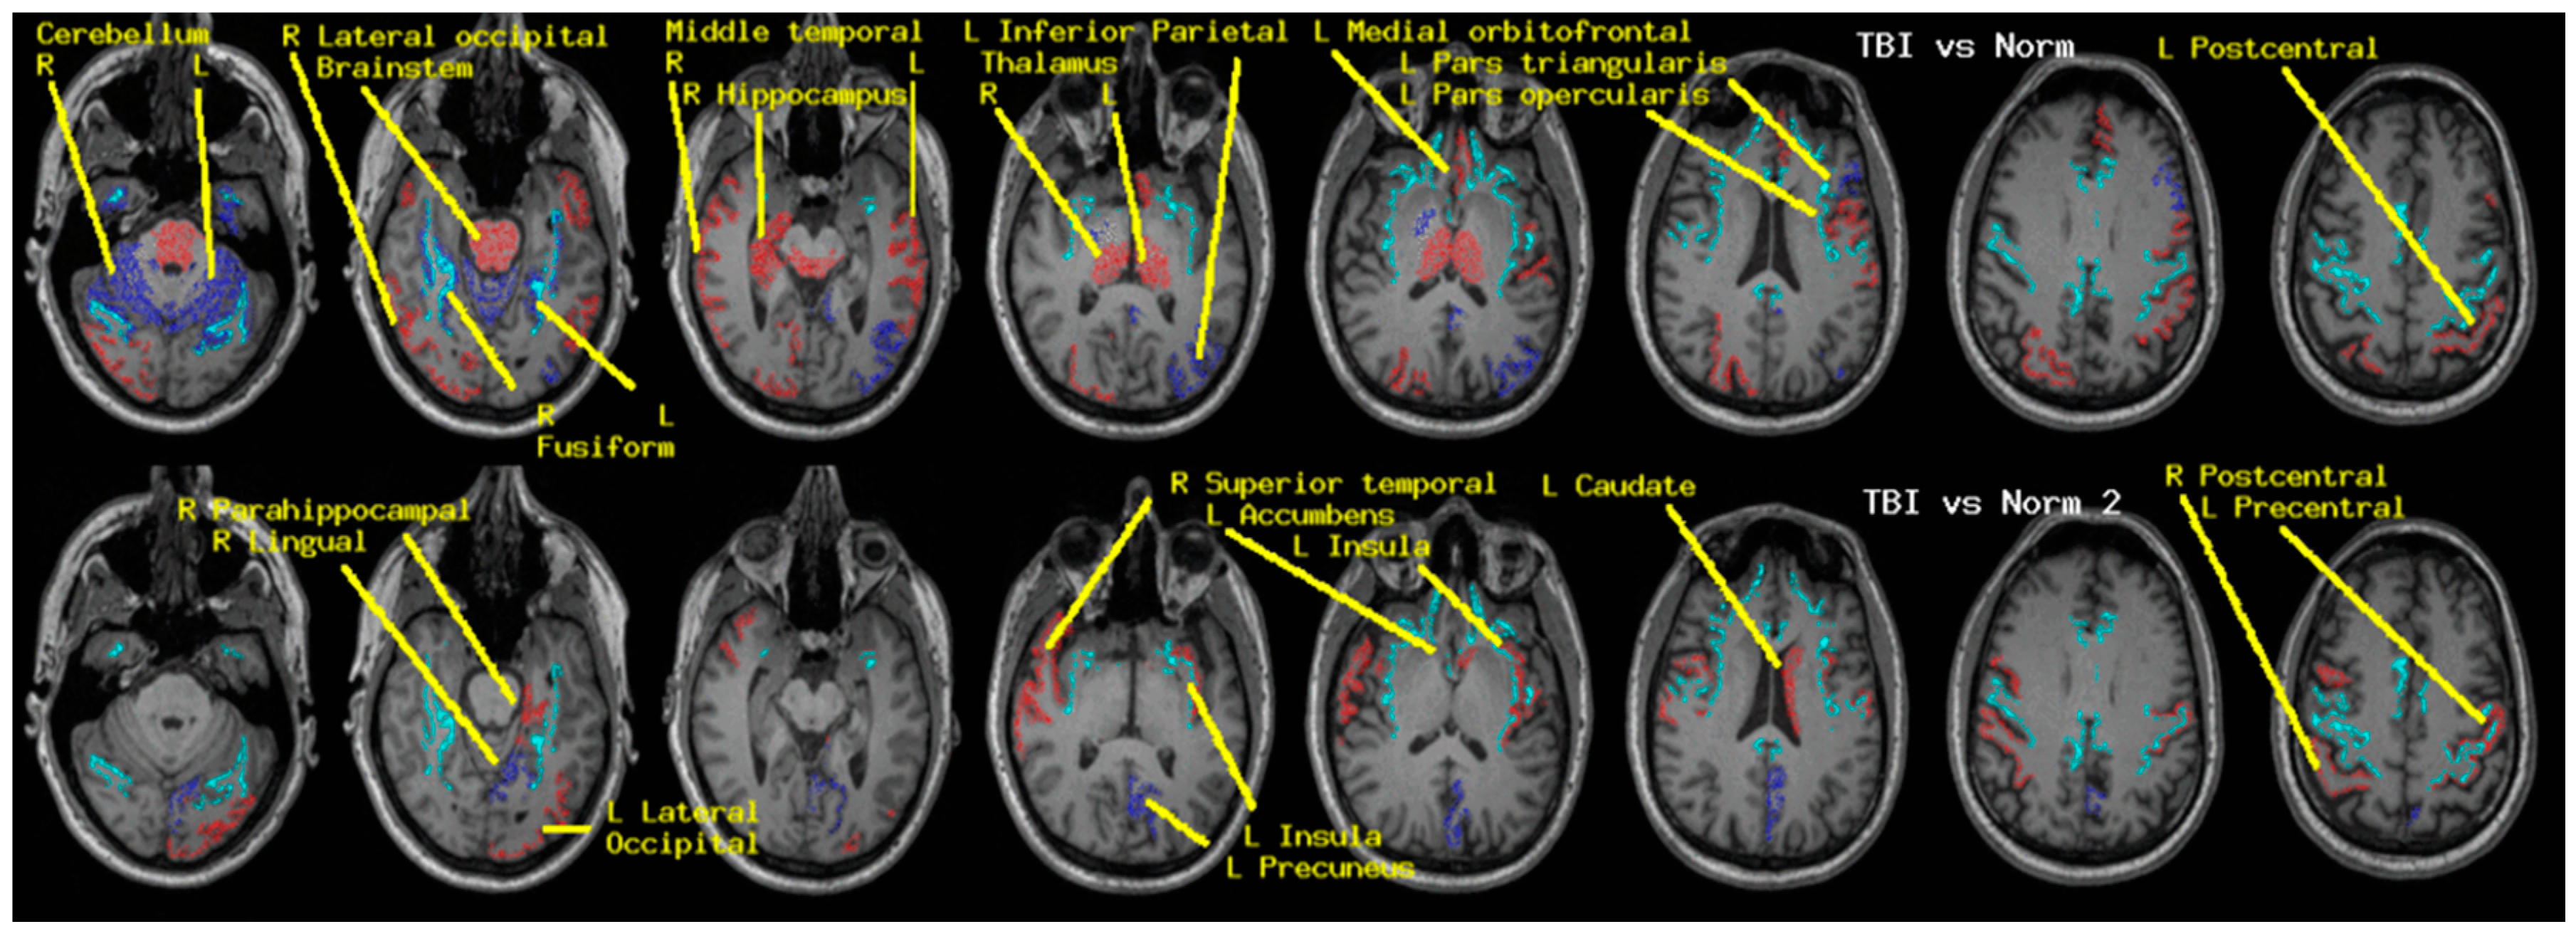

| Brain-Stem | ++ | |

|---|---|---|

| Left | Right | |

| Accumbens | - | |

| Cerebellum | + | ++ |

| Caudate | -- | |

| Hippocampus | -- | |

| Pallidum | + | |

| Thalamus | -- | -- |

| fusiform | ++ | + |

| inferior parietal | + | |

| insula | -- | |

| isthmus cingulate | ++ | |

| lateral occipital | - | -- |

| lingual | ++ | |

| medial orbito-frontal | - | |

| middle temporal | - | -- |

| para-hippocampal | -- | |

| pars opercularis | - | - |

| pars triangularis | + | |

| peri-calcarine | - | |

| postcentral | - | - |

| precuneus | + | |

| precentral | - | |

| superior parietal | - | |

| superior temporal | -- | |

| transverse temporal | - | |